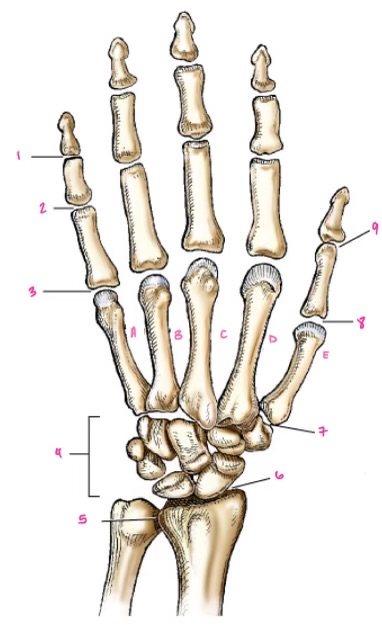

1

1

Hamate

2

2

Capitate

3

3

pisiform

4

9

Trapezoid

5

10

Trapezium

6

11

Scaphoid

7

14

Lunate

8

15

Triquetrum

9

16

Pisiform

10

17

Capitate

11

18

Hamate

1

Distal interphalangeal

13

2

Proximal Interphalangeal

14

3

Metacarpophalangeal

15

4

Intercapals

16

5

Distal radioulnar

17

6

Radiocarpal

18

7

Carpometacarpals

19

8

Metacarpophalangeal

20

9

Interphalangeal

7

Trapezoid

22

8

Trapzium

23

9

Capitate

24

10

Scaphoid

25

11

Lunate

26

13

Carpus

27

14

Triquetrul

28

15

Hamate

29

16

Metacarpus

30

17

Phalanxes